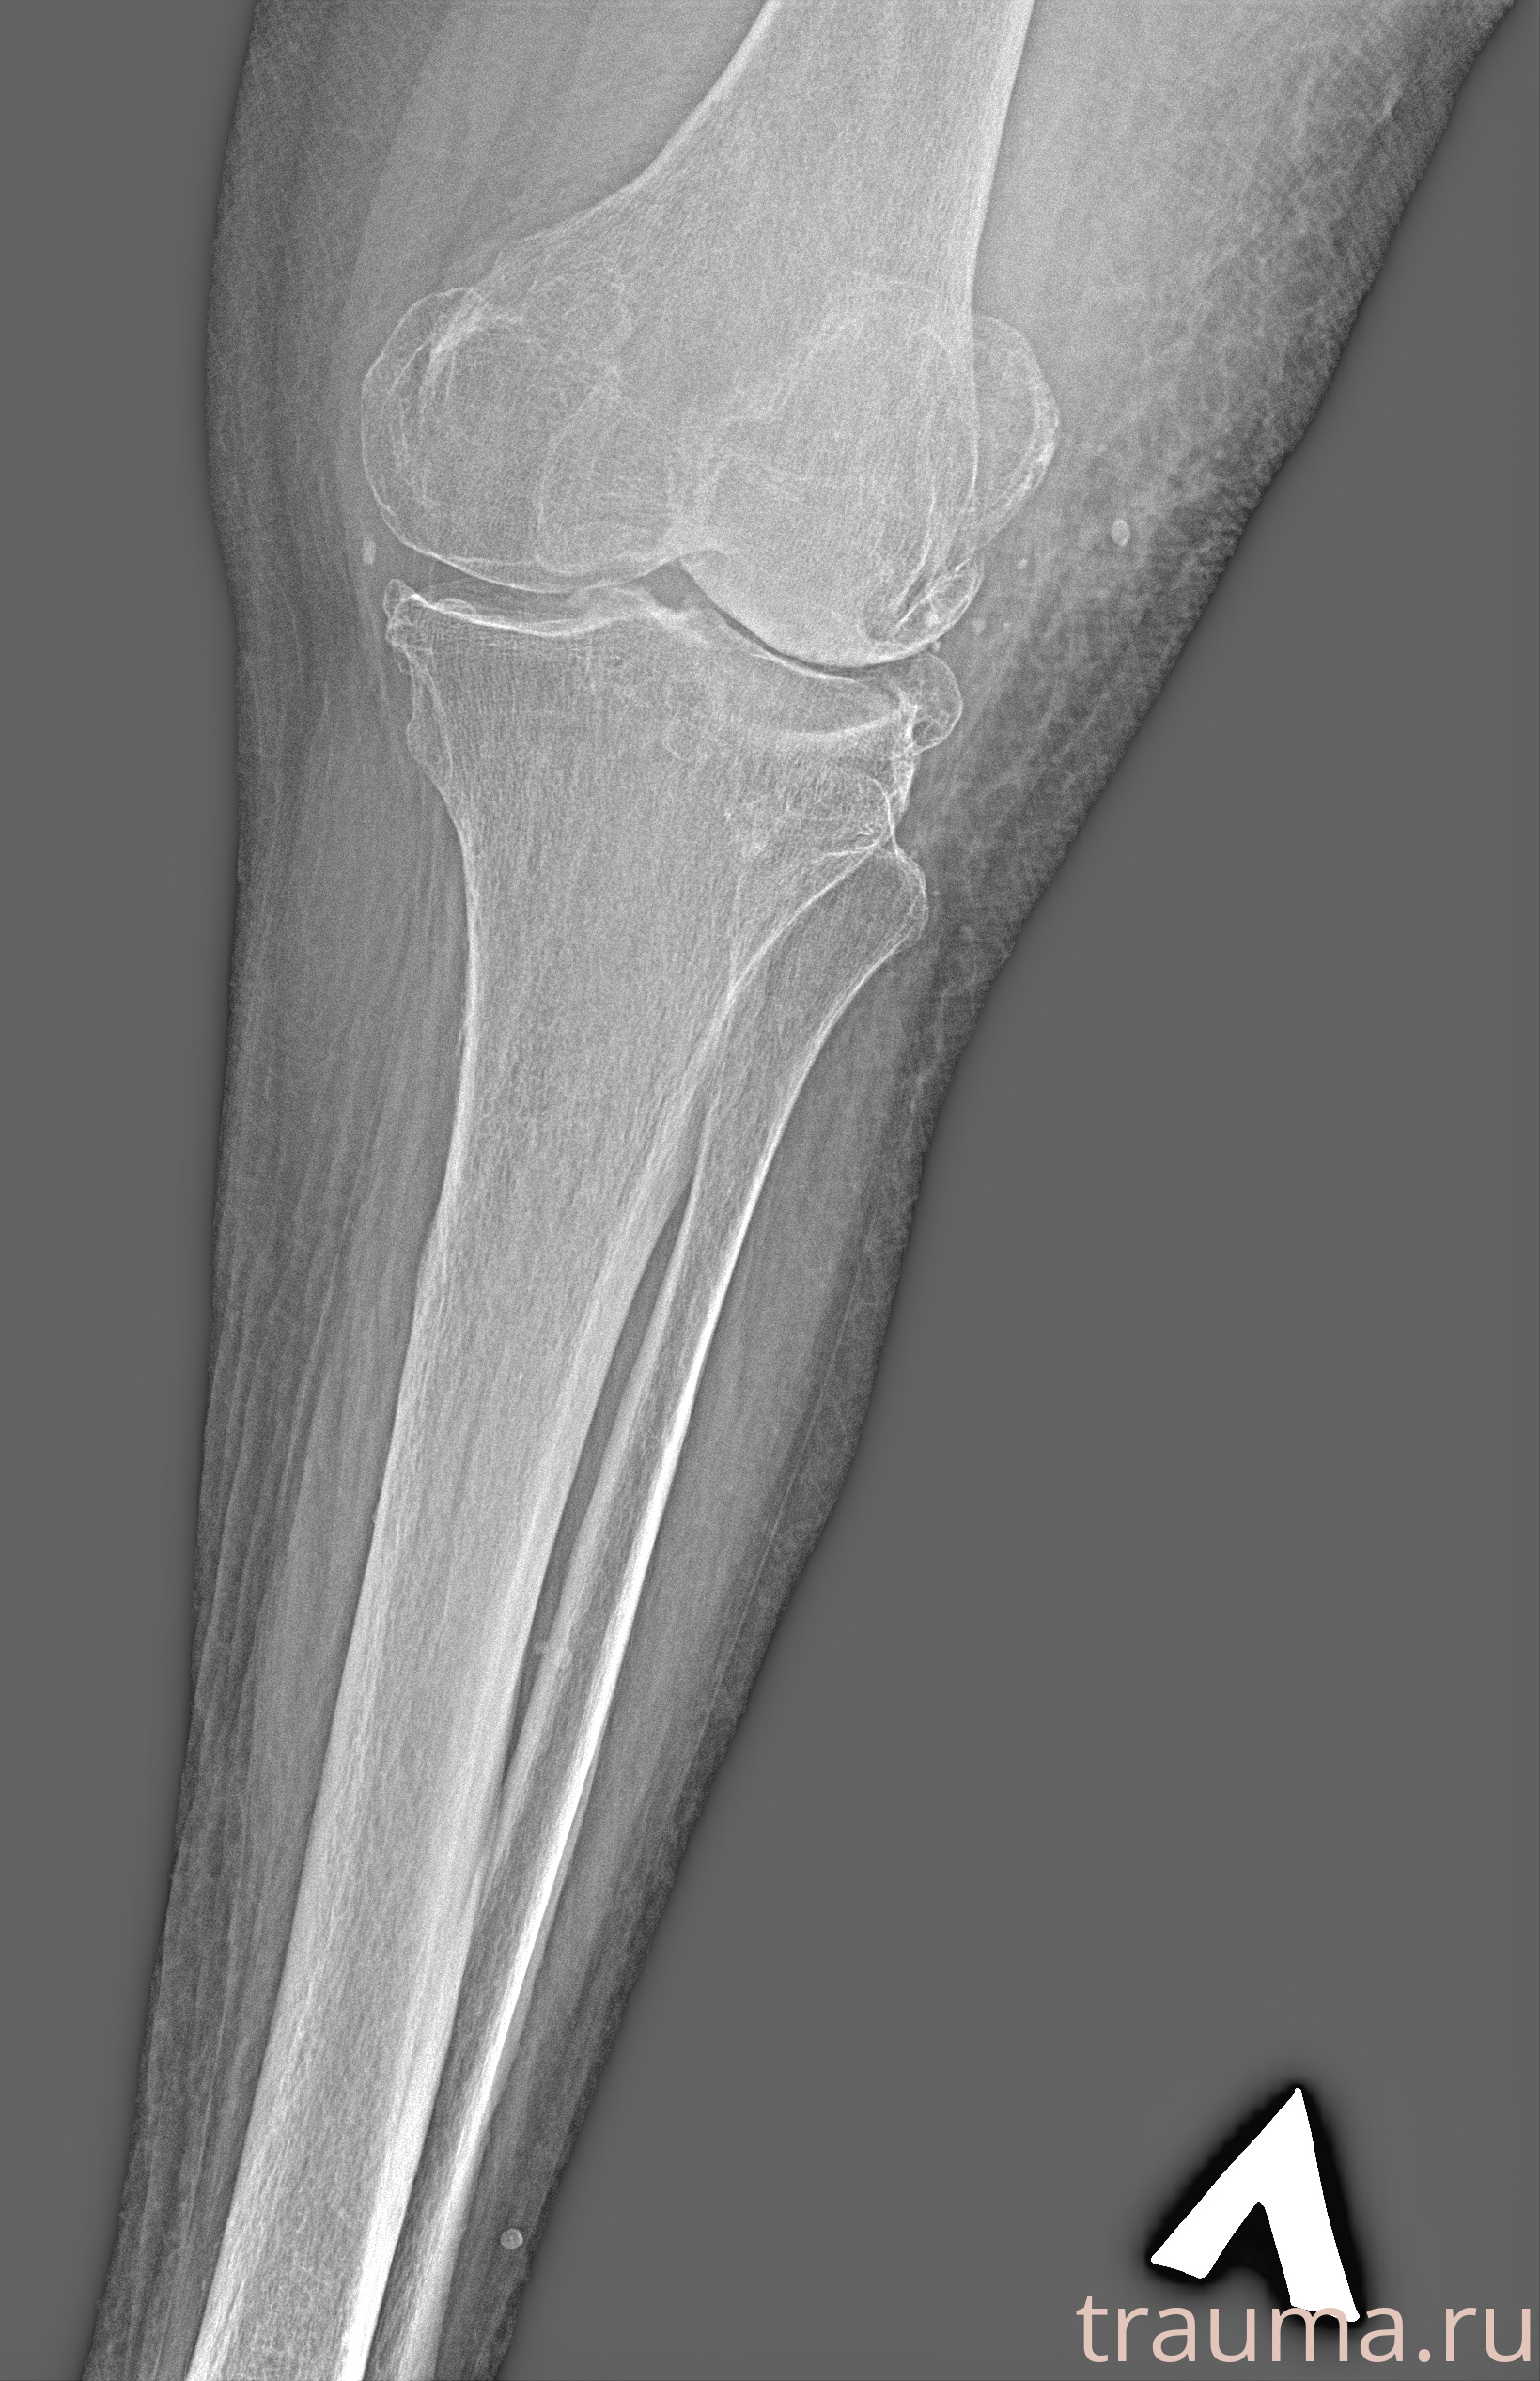

Рентген на дому: по вашему адресу приезжает врач-рентгенолог, травматолог-ортопед с мобильным рентгеновским аппаратом, проводит диагностику травмы или заболевания, делает необходимые рентгенограммы, дает рекомендации по дальнейшему лечению. Получить качественные снимки в домашних условиях возможно благодаря уникальной методике, разработанной МосРентген Центром для института  Склифосовского